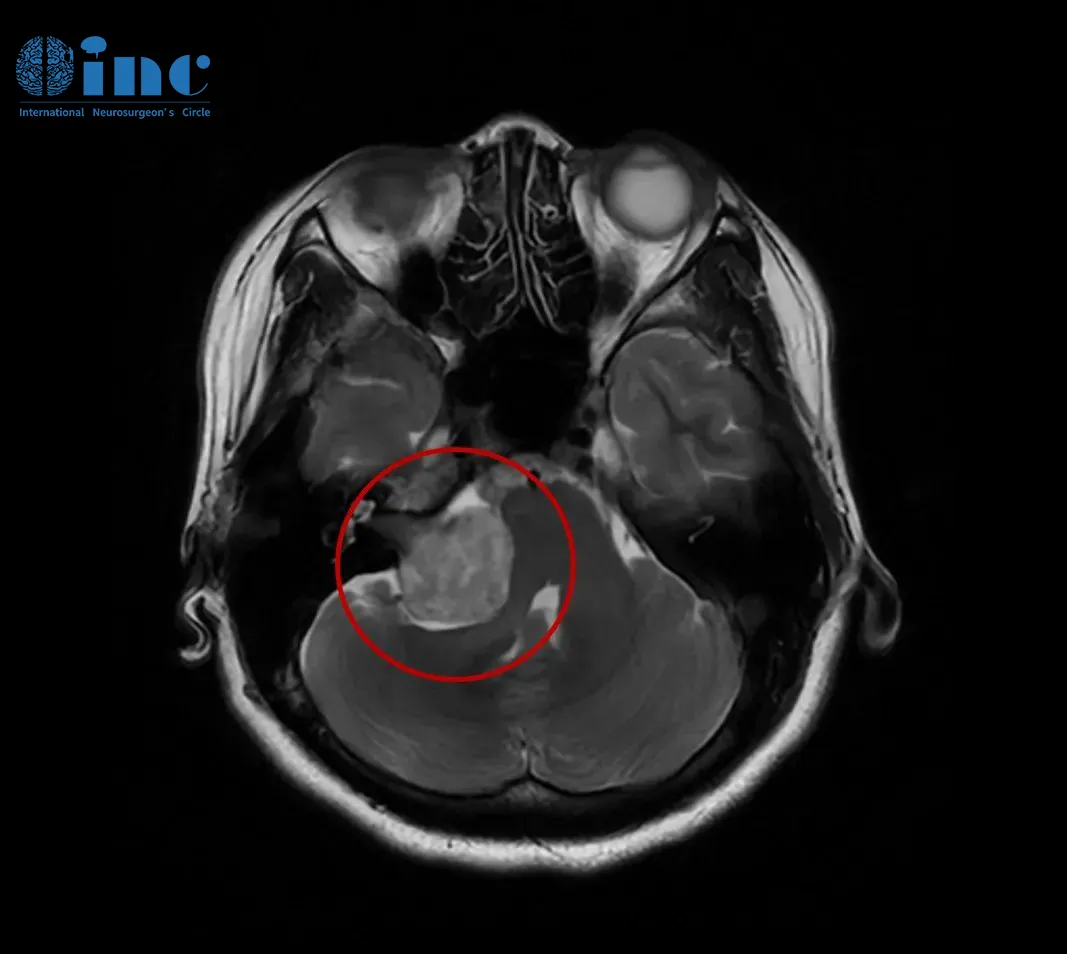

影像学检查显示:矢状位CISS序列可见导水管入口明显狭窄,IRTSE序列显示导水管内脑脊液流动正常,术前T2加权像显示侧脑室宽度正...